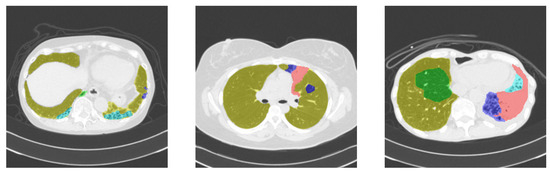

Lung Opacity Segmentation in Chest CT Images Using Multi-Head and Multi-Channel U-Nets with Partially Supervised Learning

by Shingo Mabu, Takuya Hamada, Satoru Ikebe and Shoji Kido

Appl. Sci. 2025, 15(19), 10373; https://doi.org/10.3390/app151910373 - 24 Sep 2025

There has been a large amount of research applying deep learning to the medical field. However, obtaining sufficient training data is challenging in the medical domain because annotation requires specialized knowledge and significant effort. This is especially true for segmentation tasks, where preparing [...] Read more.

There has been a large amount of research applying deep learning to the medical field. However, obtaining sufficient training data is challenging in the medical domain because annotation requires specialized knowledge and significant effort. This is especially true for segmentation tasks, where preparing fully annotated data for every pixel within an image is difficult. To address this, we propose methods to extract useful features for segmentation using two types of U-net-based networks and partially supervised learning with incomplete annotated data. This research specifically focuses on the segmentation of diffuse lung disease opacities in chest CT images. In our dataset, each image is partially annotated with a single type of lung opacity. To tackle this, we designed two distinct U-net architectures: a multi-head U-net, which utilizes a shared encoder and separated decoders for each opacity type, and a multi-channel U-net, which shares the encoder and decoder layers for more efficient feature learning. Furthermore, we integrated partially supervised learning with these networks. This involves employing distinct loss functions to both bring annotated regions (ground truth) and segmented regions (predictions) closer, and to push them apart, thereby suppressing erroneous predictions. In our experiments, we trained the models on partially annotated data and subsequently tested them on fully annotated data to compare the segmentation performance of each method. The results show that the multi-channel model applying partially supervised learning achieved the best performance while also reducing the number of weight parameters. Full article